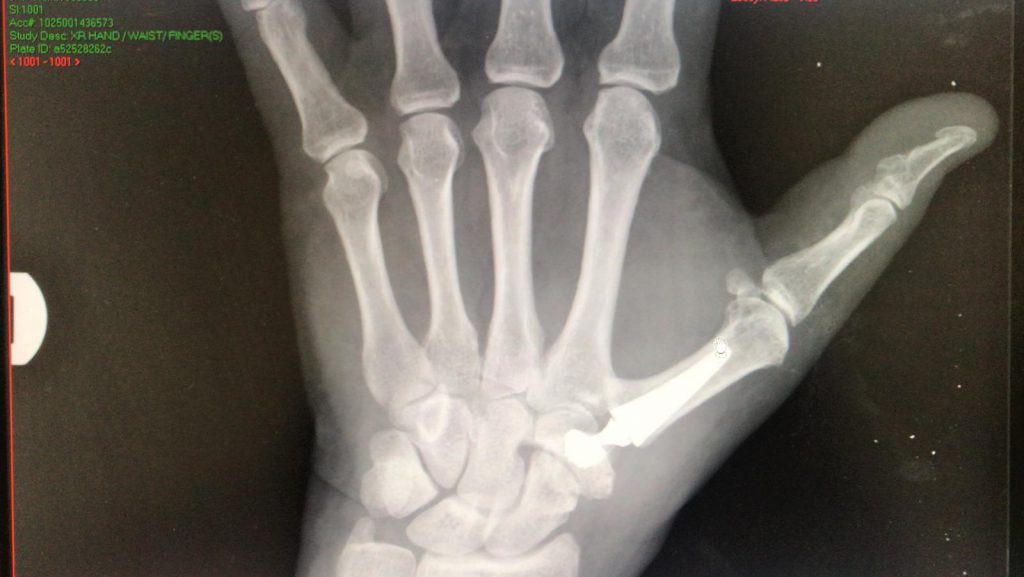

2) החלפת מפרק קרפו מטקרפוס בשתל (ראו תמונות למטה)

ד״ר שטבון מביא איתו מצרפת ניסיון של עשרות ניתוחי החלפת מפרק בסיס אגודל. הפרוצדורה הניתוחית של החלפת מפרק פותחה בצרפת לפני כ-20 שנה ועכשיו היא מיושמת בישראל באישור משרד הבריאות אבל רק במסגרת ניתוחים פרטיים. למפרקים מלאכותיים יש יתרון של חזרה מהירה לתפקוד מלא של אגודל, ללא הגבלה ובתהליך החלמה קצר.

צילום רנטגן של שתל שהוחדר בניתוח של ד״ר שטבון

השתל מחליף את המפרק השחוק